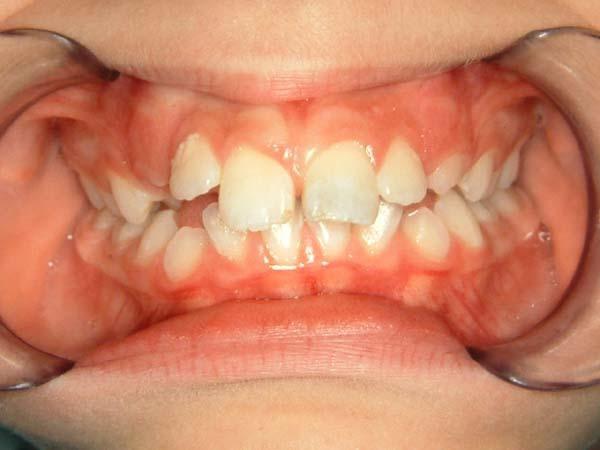

1η περίπτωση

Αρχική οδοντοσκελετική κατάσταση παιδιού με προγναθισμό άνω γνάθου και έντονη οριζόντια πρόταξη άνω τομέων Η σημασία της στοματικής υγιεινής και ορθοδοντικής

026

027 Αμέσως μετά το τέλος της ορθοδοντικής θεραπείας. Οι αλλαγές στην οδοντική του σύγκλειση αλλά και στο πρόσωπο είναι εμφανείς 15 χρόνια μετά την αρχική περάτωση της θεραπείας, το αποτέλεσμα παραμένει σταθερό και ο ασθενής απέκτησε ένα υγιές και αρμονικό χαμόγελο και πρόσωπο. Η σημασία της στοματικής υγιεινής και ορθοδοντικής πρόληψης